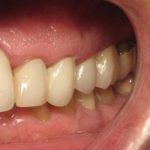

Anthony A.

This patient had only a few remaining infected teeth, but didn’t want to settle for just a denture.  Placed multiple implants and provided a secure fixed option which allowed him to not only chew better but to smile again.